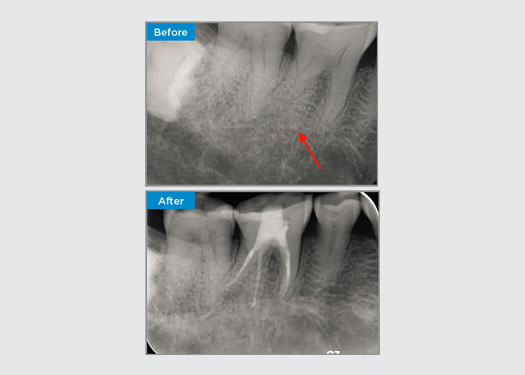

Der Patient stellte sich mit einer asymptomatischen apikalen Parodontitis an Zahn 34 vor. Auf dem präoperativen Röntgenbild war Zahn 34 mit zwei sichtbaren Wurzeln zu erkennen. Ein DVT-Scan bestätigte jedoch, dass es sich um einen dreifach verwurzelten Prämolaren handelte und dass sich die Kanäle in der Mitte der Wurzel in drei Kanäle aufteilten. Für diesen empfindlichen Zahn ist eine sorgfältige Feilenauswahl entscheidend.

Dr. Jack Lin, Endodontist, Sydney, NSW Australien

In dieser Situation ist die Erhaltung der Zahn-/Wurzelstruktur von entscheidender Bedeutung, um das Risiko von Vorsprüngen, Verschiebungen, Abrissen, Perforationen und Wurzelfrakturen zu verringern. Fallauswahl, Diagnose und Behandlungsplanung sind wichtig. Die Auswahl von endodontischen Feilen, die flexibel und effizient sind und die natürliche Wurzelanatomie respektieren, ist entscheidend.